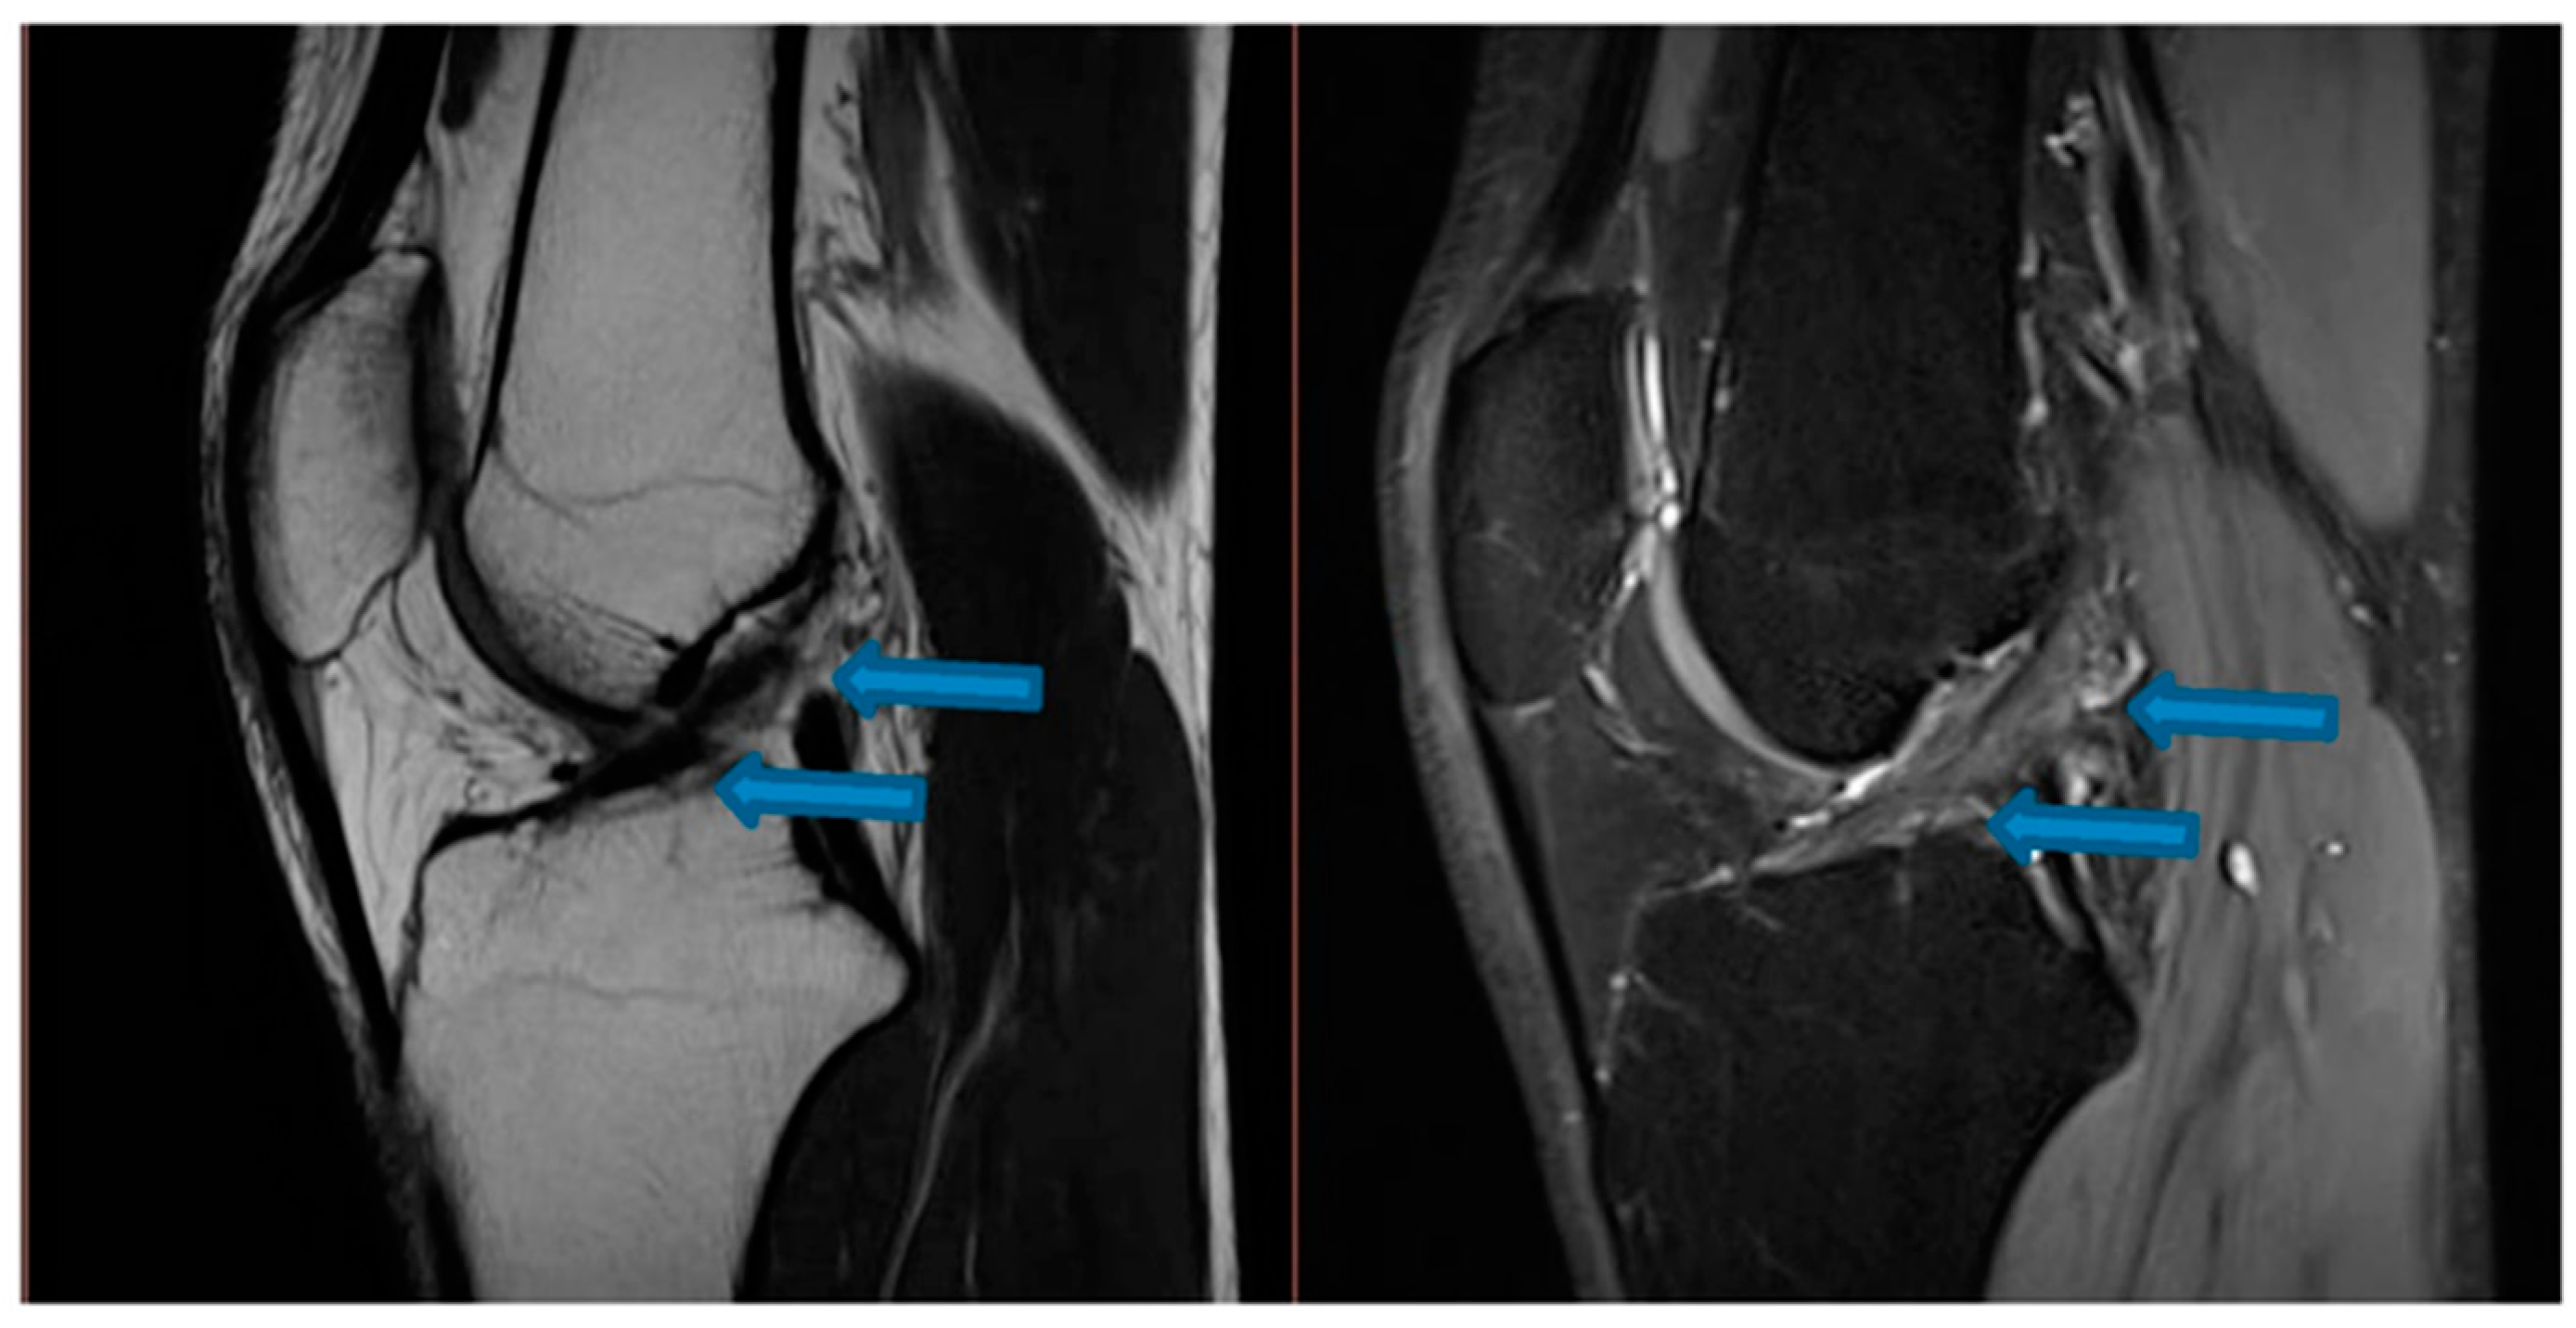

| 14 August 2021 | MRI scans demonstrating signs of complete ACL healing |